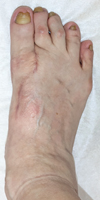

Her right foot exhibited a hallux varus deformity, and the second and third toes were dislocated dorsally (Figure 1(a)). Skin erosion at the dorsal aspect of the proximal interphalangeal joint of the second and third toes was observed. The range of motion (ROM) of the first MTP joint was 40° in dorsiflexion and 10° in plantarflexion. There was a tender callosity at the plantar aspect of the second metatarsal head. On plain radiographs, the hallux valgus angle was -24°, and the IMA was 0° (Figure 1(b)). The joint space at the first MTP joint was maintained.

(a)

(b)